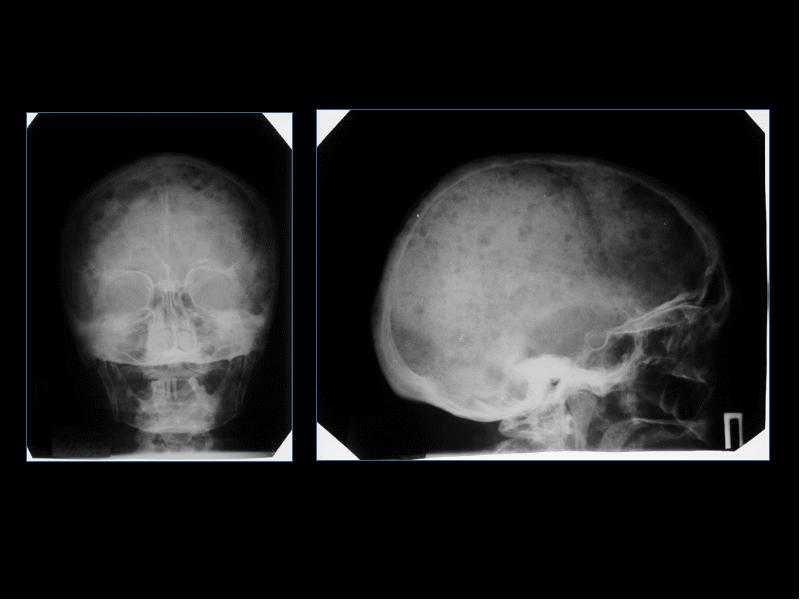

Лучевая диагностика доброкачественных